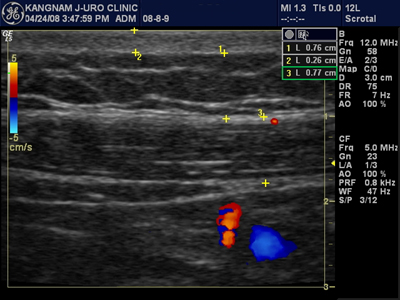

<ÇÇÇÏÁö¹æÃþÀ» ÃÊÀ½ÆÄ¸¦ ÀÌ¿ëÇØ ÃÔ¿µÇÑ »çÁø>